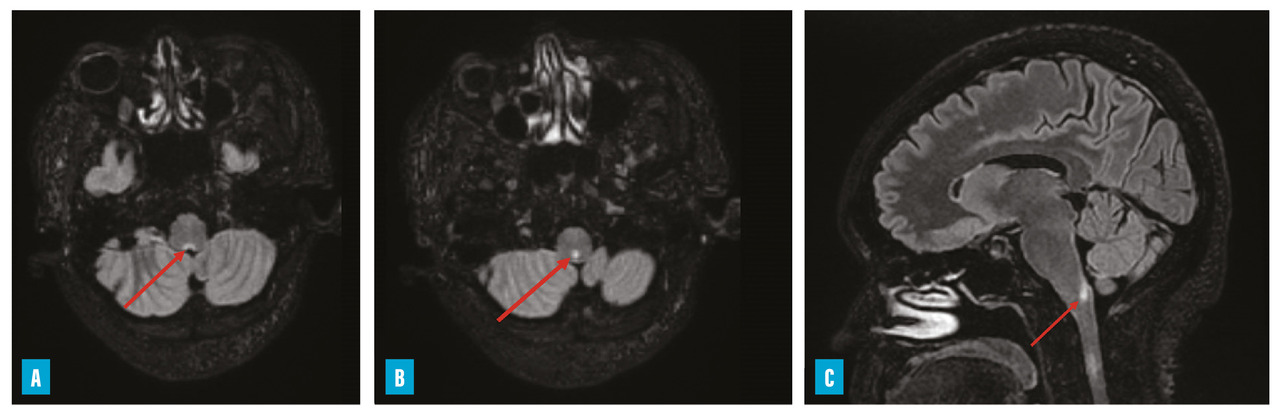

– hoquet et vomissements incoercibles qui peuvent être isolés à la phase initiale (atteinte de la paroi postérieure du 4e ventricule dite area postrema) [fig. 2] ;

Chez les adultes, la névrite optique constitue le mode d’entrée majoritaire dans la maladie (61 % dans la cohorte française MOGADOR).13 Elle est volontiers, comme dans la NMO, bilatérale et sévère. Un œdème papillaire est possible et le segment antérieur du nerf optique est préférentiellement touché. Contrairement à la NMO, l’atteinte du chiasma est rare et la récupération est meilleure. Concernant les myélites, l’atteinte du cône terminal est plus fréquente et doit faire évoquer le diagnostic (fig. 3) ; les myélites « courtes » ne sont pas rares (presque 40 % dans la cohorte française).13